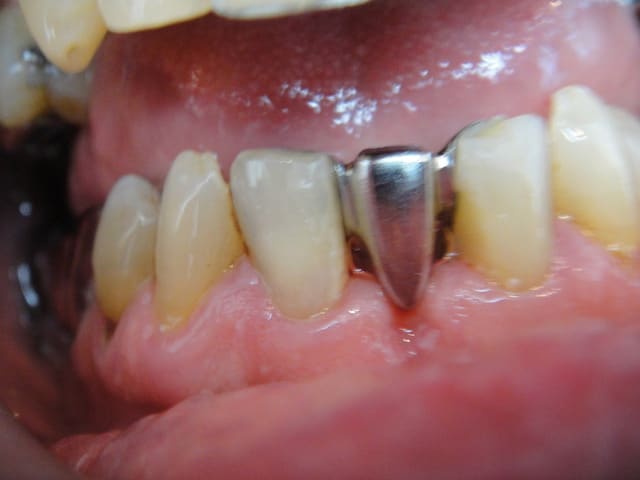

patient de 70 ans qui ne souhaite pas d'implant.

pas de parafonction à signaler ni de demande esthétique importante.

je vais faire un bridge collé avec pins dentinaires et fraisage amelaire (armature métal scellée)

32 et 42 sont parodonto solides.

prendriez vous les canines?

ça ne me parait pas indispensable.